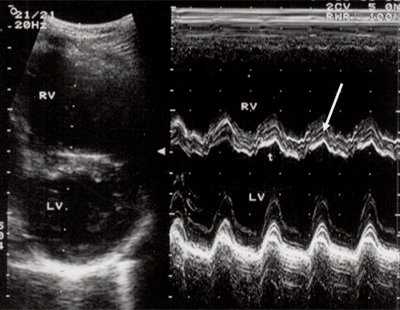

Для левого желудочка признаком объемной перегрузки являются увеличение полости левого предсердия и желудочка, а также экскурсии межжелудочковой перегородки и миокарда задней стенки левого желудочка (рис. 4).

Рис. 4. Объемная перегрузка левых отделов сердца. В- и М-сканирование. Отмечается усиление экскурсии межжелудочковой перегородки и миокарда задней стенки левого желудочка.

IVS - межжелудочковая перегородка, MLV - миокард левого желудочка, LV и RV - левый и правый желудочек.